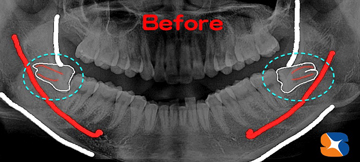

Dr:「(レントゲンで確認後)特に左の親知らずの歯(向かって右)が、横向きに倒れて、骨の中に深く埋まっています。

※骨の中に埋もれている割合+横向き度合い+根の曲がり具合(上の写真)→抜歯の難レベル(A→B→C→ウルトラC)

が決まります。今回のケースは、正に“ウルトラC”でした。出発まで残りあと僅かですが、最後まで責任をもって経過を見ていきます。本当によく頑張られました。